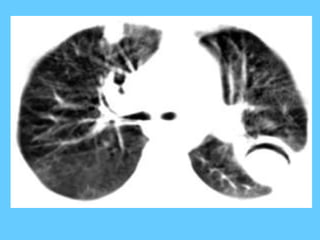

Pulmonary alveolar microlithiasis is a rare condition characterised by a

diffuse bilateral filling of the majority of alveoli by calcific concretions

called "Calcospherites".

The aetiology and pathogenesis are obscure; a familial incidence has

been reported in several instances. Pulmonary alveolar microlithiasis is

rare and less than 100, cases have been reported in the world literature.

The radiological picture that is very characteristic shows bilateral sand-

like micro nodules of calcific density, usually most marked in the middle

and lower zones with relative sparing of the apices. Although the

radiological picture is diagnostic, many cases are mistaken for miliary

tuberculosis, silicosis, berylliosis, sarcoidosis, haemosiderosis, fungal

infections and carcinomatosis. Most patients remain symptom-free for

many years despite extensive radiological changes. In over half the

reported cases, a familial incidence has been demonstrated almost

invariably among Siblings and only in two instances in a parent and

child; cases in infants have also been reported. A genetic factor has

been postulated because of familial occurrence.

It has been suggested the possibility of congenital error of metabolism

at the level of alveolar surface membrane, possibly an enzymatic fault,

resulting in the precipitation of calcium in the presence of undue

alkalinity.

Microlithiasis alveolaris